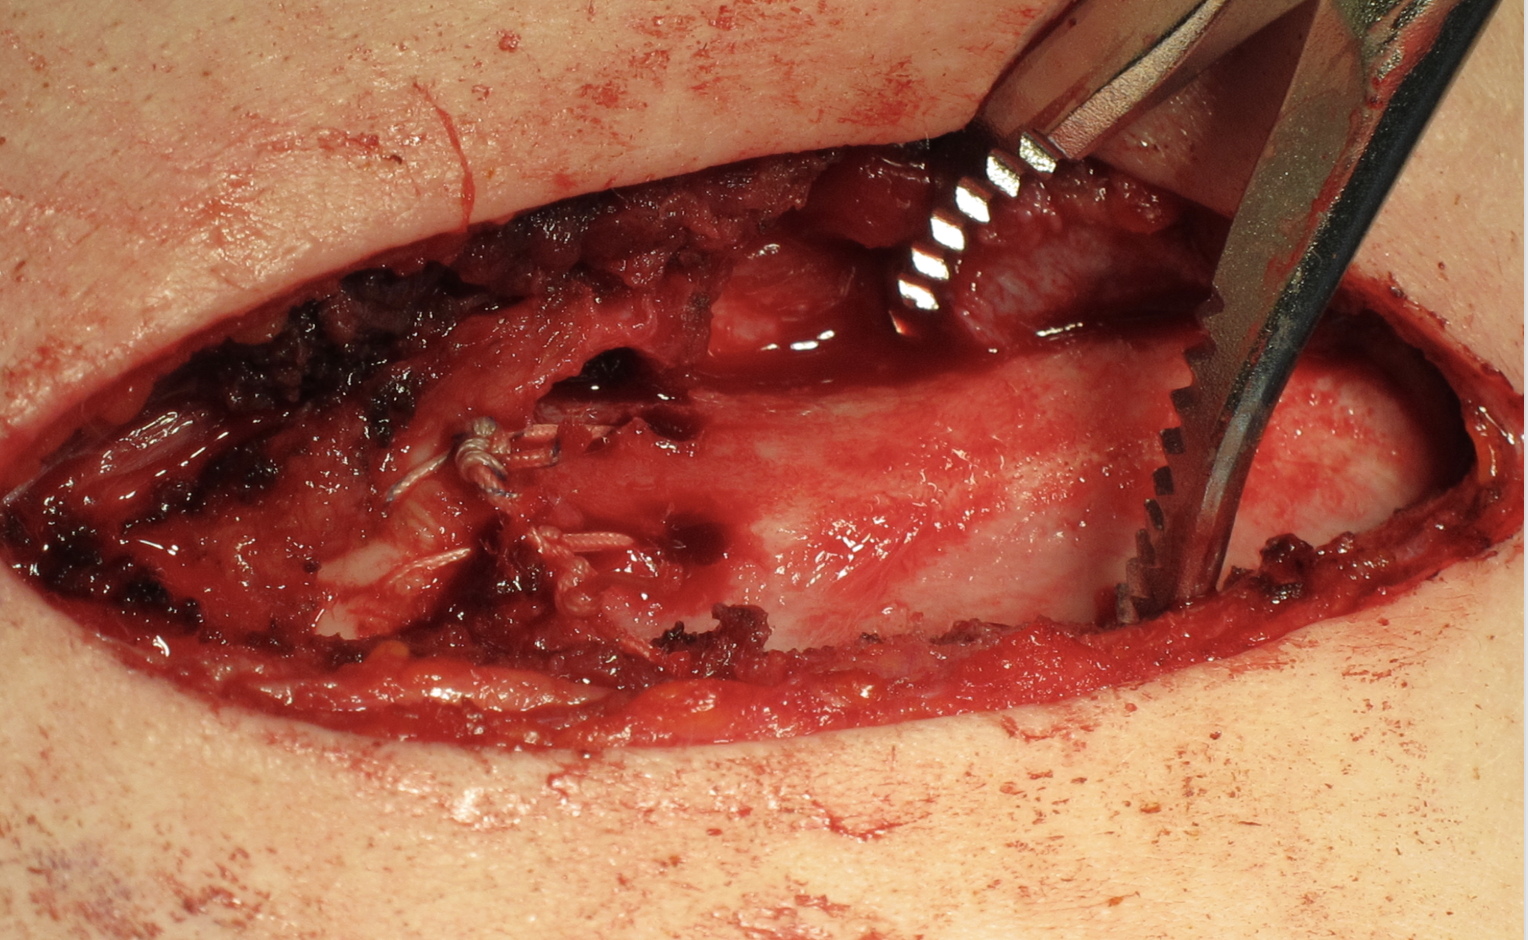

Open reduction of acute posterior sternoclavicular joint dislocation

Drill holes in manubrium and medial clavicle

Figure of 8 suture fixation